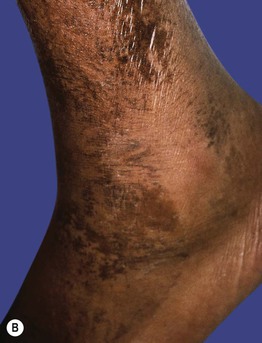

Fig. 43.7 Pellagra. A Hyperpigmentation with desquamation of the dorsal aspects of the hands and forearms. B Hyperpigmented desquamation of the distal lower extremity. Note the shiny shellac-like appearance on the lateral ankle.

Fig. 43.8 Zinc deficiency. Genetic (acrodermatitis enteropathica) (A–D) and acquired (E, F) forms. Both have erythema with erosions (A, E) as well as crusting (C, E, F) and desquamation (A, D–F). Lesions favor the acral and periorificial sites, and pustular paronychia may also be seen (B). Acrodermatitis enteropathica most often presents in infancy (A, B), but rarely, it is not diagnosed until later childhood, as in the case of this 11-year-old boy (C, D). A–D, courtesy, Julie V. Schaffer, MD.